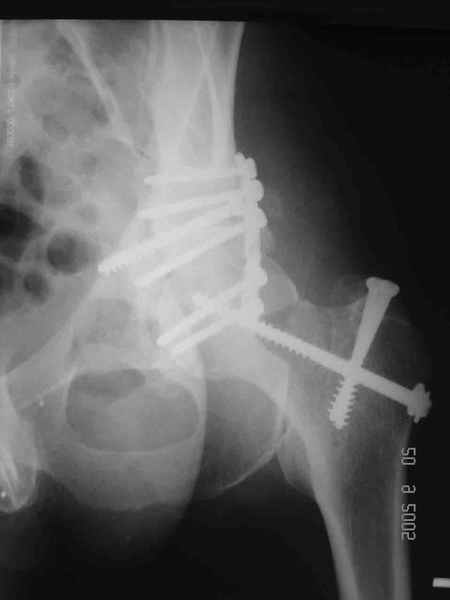

Послеоперационный снимок прямой 5/05/03

|

Больной 18 мая 2003 года в автоаварии получил перелом левой вертлужной впадины, вывих бедра. Госпитализирован в один из стационаров области.Вывих вправлен. В последствии бедро вывихивалось еще дважды. На консультацию был представлен снимок от 19.05.03г., больной переведен к нам 3.06.03г. Снимок при поступлении - перелом впадины, задне-верхний вывих бедра. 05.06.2003 г. выполнено открытое вправление вывиха левого бедра и остеосинтез стенки вертлужной впадины двумя винтами. Послеоперационный период без осложнений. Объем движений в левом тазобедренном суставе восстановился полностью. Выписан на амбулаторное лечение в удовлетворительном состоянии с рекомендациями 3 месяца ходить на костылях без нагрузки на оперированную конечность. На контрольных рентгенограммах левого тазобедренного сустава 13.10.2003 г. - признаки консолидации перелома; плотность, форма головки и состояние суставных поверхностей удовлетворительные. Разрешена дозированная осевая нагрузка, на конечность с использованием дополнительной опоры. 19.12.2003 г. больной обратился с жалобами на боли в левом тазобедренном суставе. На рентгенограммах левого тазобедренного сустава 19.12.2003 г., 20.02.04г. - асептичекий некроз головки бедра. 5.04.04г. - эндопротез. Сейчас ходит без трости, не хромает. Особенность эндопротезирования - при удалении винтов прослежена линия перелома заднего края впадины и предложено установить чашку несколько меньшего диаметра, чтобы она была покрыта несломанной частью.